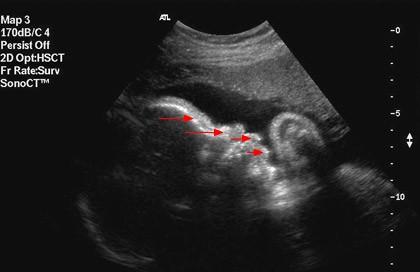

Profil obličeje při III. ultrazvukovém screeningu ve 30. týdnu těhotenství. Šipky zleva doprava označují: čelo, nos, horní a dolní ret.